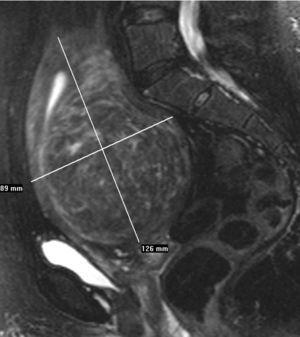

Se hizo una ecografía transvaginal (TV), que puso de manifiesto un mioma único intramural en la cara posterior uterina, una RM pélvica y una angio-RM, en la que se observaron unas arterias uterinas normales (fig. 2A).

Figura 2A. Resonancia magnética pélvica (secuencia T2 sagital). Mioma transmural de 10 cm.